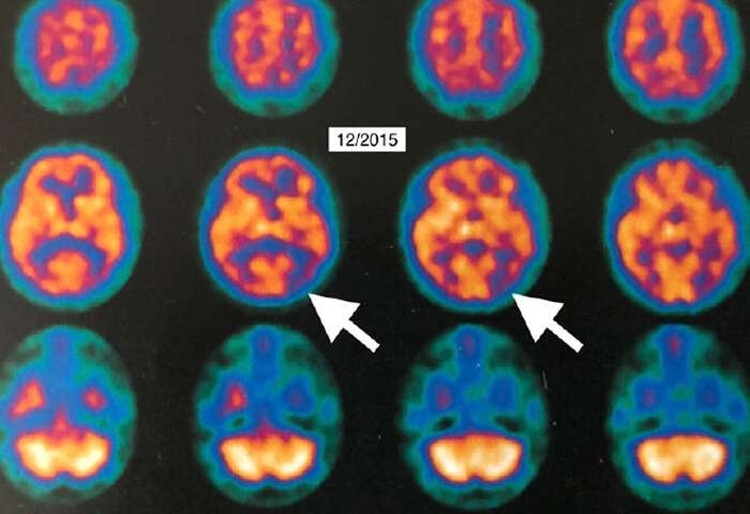

Al comparar las imágenes de la PET realizada un mes después de finalizado el tratamiento OHB con los estudios anteriores, se hallaron cambios visibles del metabolismo cerebral entre el 6,5% y el 38 por ciento.

«Demostramos la mayor mejora en el metabolismo cerebral de todas las terapias para el mal de Alzheimer«, dijo Harch a Medical Press. «En esta paciente, la OHB podría ser el primer tratamiento que no sólo detiene, sino que temporalmente revierte temporalmente el progreso de la enfermedad«.

El trabajo incluyó imágenes en 3D de la PET que reconstruyen la superficie del cerebro de la mujer, donde se pueden ver los cambios. «La PET se utiliza en el mundo como un biomarcador en oncología y cardiología para evaluar las respuestas a los tratamientos», dijo Fogarty en la página de LSU. «Ahora tenemos un sistema de biomarcación irrefutable que muestra que esta intervención tiene potencial allí donde antes no existía una esperanza real de recuperación de la demencia«.